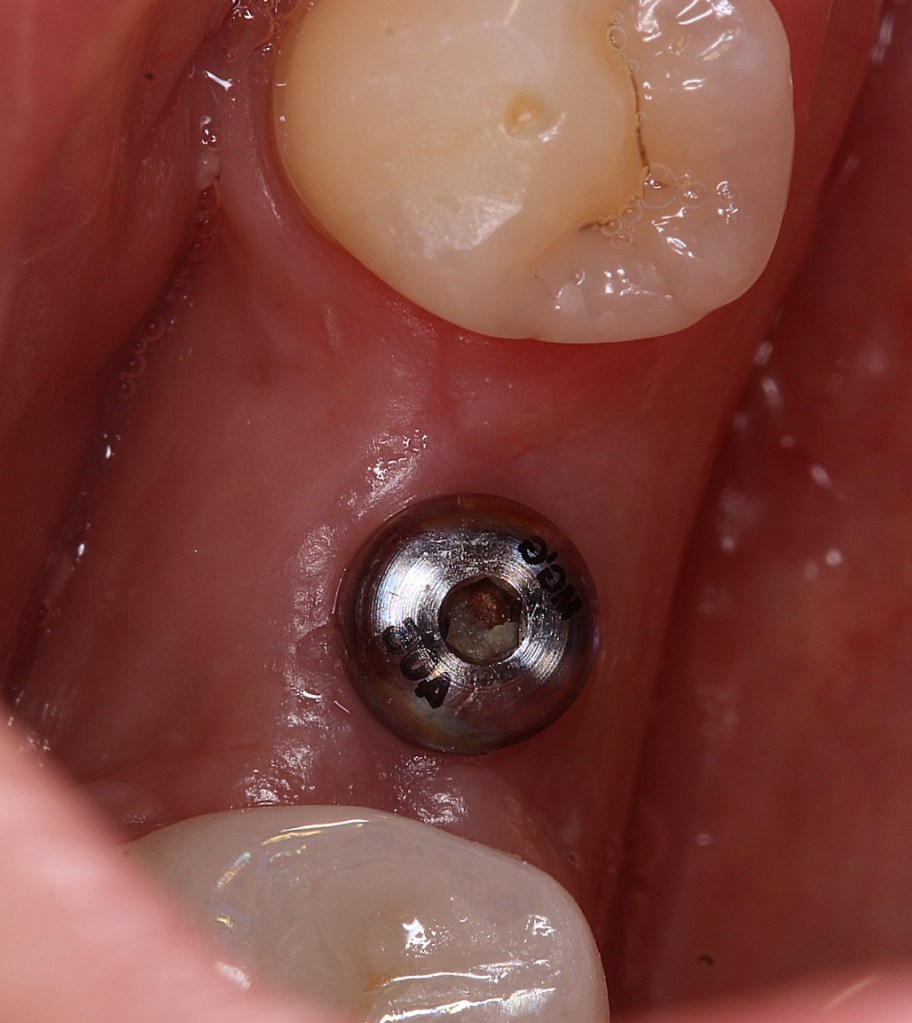

Implant Megagen Anyridge, inserat intr-o creasta atrofica, de 6,5mm latime. Simple anyridge implant placement, with bone expansion and CTG to compensate the 6,5mm bone crest.

Insufficient crest width and thin tissue